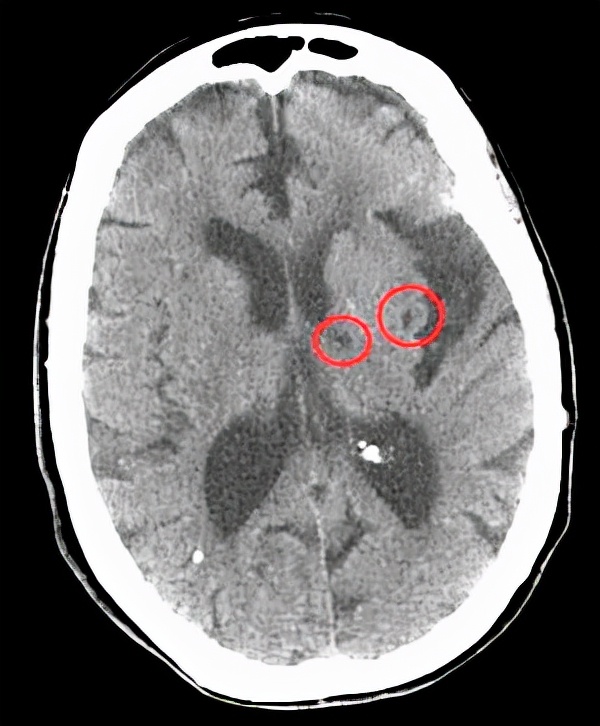

二、无症状的腔梗。

如果出现腔隙性脑梗死该怎么办呢?

当然,这个问题其实也应该分情况讨论。

如果有了具体症状,腔梗还是该治疗的,比如一侧肢体的运动感觉障碍,这个时候要小心,具体怎么治疗还是听医生的吩咐比较好。

但是如果没什么表现,仅仅是在体检或者在检查其他疾病的过程中发现有腔梗,这个时候该怎么办呢?

临床当中这种情况是很常见的,我们称为无症状的腔隙性脑梗死,对于这类患者,请您别害怕。

虽然我们称之为脑梗死,但他对我们的危害并不大,只需要改善生活方式,积极预防下一次腔梗就可以了。

需要用药吗?需要用治疗脑梗死的扩血管药物吗?是不是应该活血化瘀呢?

都不用,千万别被骗。